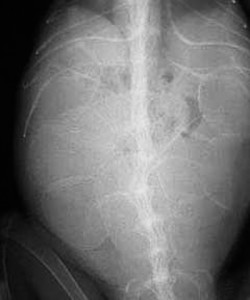

Our digital radiography machine gives us substantially better radiographs than the two above. Even though there are other factors like the amount of calcium on the eggs, and whether they are pre or post ovulatory, the difference between the old way and new way of taking radiographs is significant.

This side view is called a lateral view. The R market means this iggie was laying on her right side

This view from the top is called a dorso-ventral view. The R marker denotes the right side of this iggie.

Do you see the eggs in this radiograph of Zeke? Click on the picture for a larger version to help you visualize them. As it turns out there are 30 eggs in Zeke’s abdomen (the abdomen of an iguana is called the coelomic cavity).